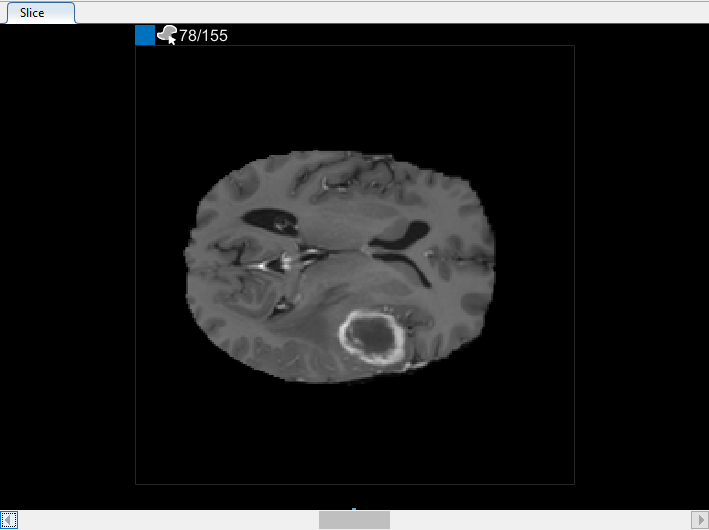

Можно также просмотреть каждый срез объема в панели Среза. Используйте ползунок в нижней части панели, чтобы переместиться от среза до среза. Вы видите опухоль на срезе 35 через срез 88. По умолчанию панель Среза отображает объем, ориентированный вдоль оси X-Y, но можно изменить это использование кнопки в разделе Orientation панели инструментов на вкладке Segmenter. Панель Среза также, где вы используете инструменты для рисования, чтобы задать маску.

В панели Среза перейдите к срезу, где объект сначала появляется, и начните помечать объект на каждом срезе с помощью инструмента для рисования. В следующем рисунке этот пример использует инструмент Paint Brush, чтобы пометить опухоль. Как ранее, можно чертить объект на каждом срезе, где это появляется, или используйте инструменты интерполяции, чтобы привлечь несколько срезов автоматически. После интерполяции можно использовать инструменты для рисования, такие как Средство стирания, чтобы изменить автоматизированную сегментацию на каждом срезе.